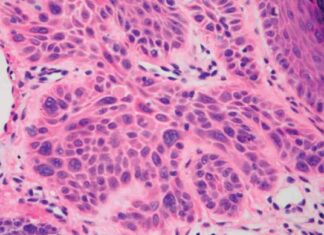

Starving Cancer Cells: Scientists’ Approach to Treating Cancer

Scientists are constantly searching for new and innovative ways to treat cancer, and one approach that has garnered significant attention is starving cancer cells. Like all living things, cancer cells require nutrients to survive...